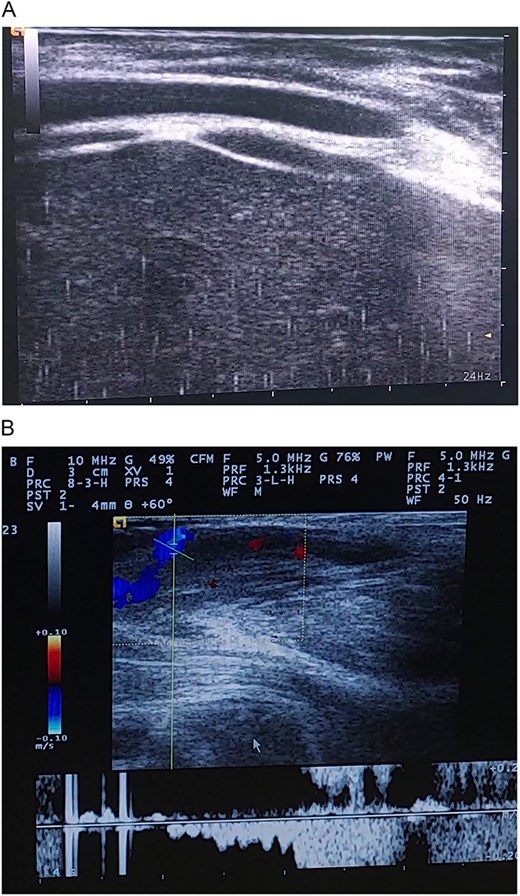

Color and spectral Doppler ultrasonography revealed a multicystic, low-flow vascular lesion (Fig. 2). Based on these findings, a diagnosis of sporadic, unifocal, slow-flow VM was established. Pre-procedure coagulation screening, including prothrombin time, and baseline renal function tests were conducted.

(A and B) Ultrasound images demonstrating cystic vascular spaces with non-pulsatile venous flow.